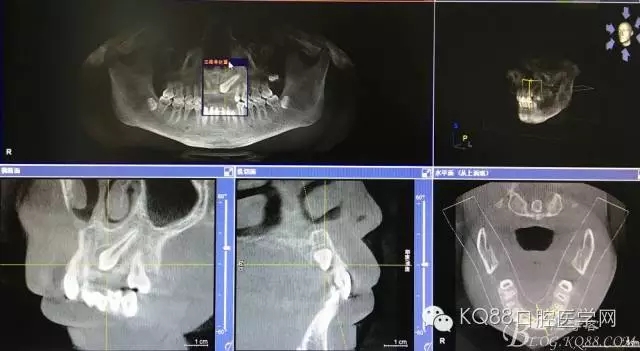

圖1.術(shù)前的cbct影像檢查:23位于腭側(cè)、牙齒位置比較高。

圖2.全景片影像檢查:23牙冠的遠(yuǎn)中還有一顆22畸形牙、及63滯留

圖3.冠向切面:23牙冠緊鄰21的牙根

圖4.縱剖面顯示23位于腭側(cè)

圖5.水平切面觀23位于腭側(cè)